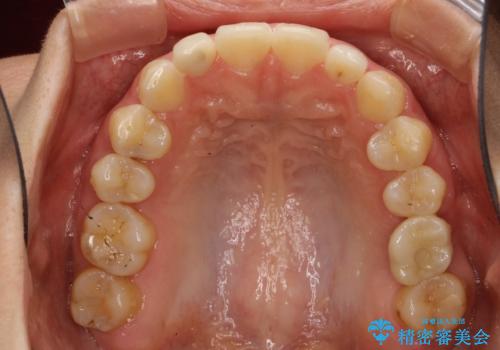

Invisalign インビザライン lite ライト 隙っ歯の改善

- マウスピース矯正による隙間の閉鎖を計画しました。

簡便な処置のため、ライトを選択しました。

かみ合わせが深くない空隙歯列は、最も簡単にその改善が見込まれます。